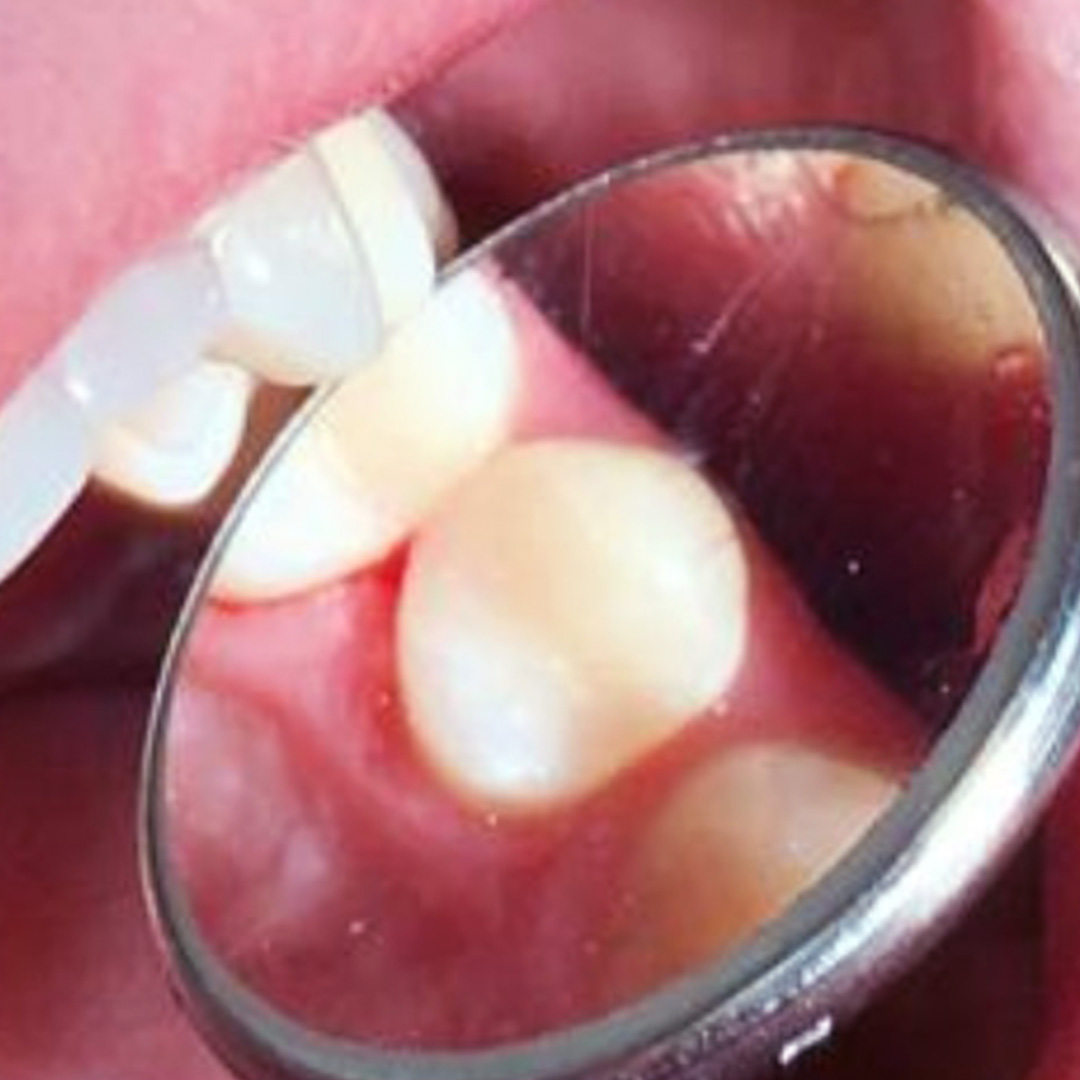

До и после лечения

Пломбы из светоотверждаемых композитов отличаются от пломб химического отверждения тем, что застывают под воздействием УФ-лучей. Светокомпозит обладает высокой эстетикой, не отличается от натурального оттенка зуба. Среди других преимуществ: гипоаллергенность, высокая прочность и безопасность, быстрая фиксация, долговечность.